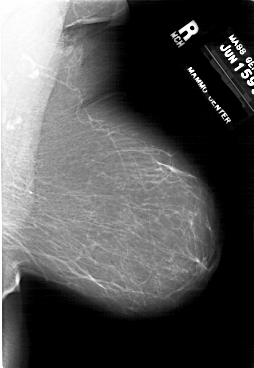

Со старением железистая ткань постепенно исчезает: прозрачность жировой ткани становится преобладающей с несколькими каркасами, связанными с опорными волокнистыми структурами.

Жирная (не плотная) грудь

Умеренно плотная грудь

Плотная грудь

Маммограммы представляют собой изображения структур, проецируемых на плоскость: плотная грудная маммограмма, следовательно, состоит из многих других структур, которые необходимо проанализировать, чем более жирная, пустая грудь. По этой причине диагностировать рак молочной железы труднее для моложе, чем для пожилых женщин.

Нажмите на миниатюрные картинки, чтобы получить увеличенный размер.